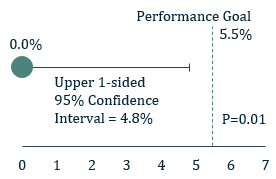

Figure 1: 1° Endpoint - Effective closure

- The 1° endpoint of ICE LAA was significant peri-device leak (>5 mm) based on the 45-day post-implant TEE and assessed by the echocardiographic core laboratory

- The 1° endpoint was met. The rate of leak >5 mm was 0.0% with an upper one-sided 95% confidence interval of 4.8%, which is lower than the prespecified performance goal of 5.5% (P=0.01).